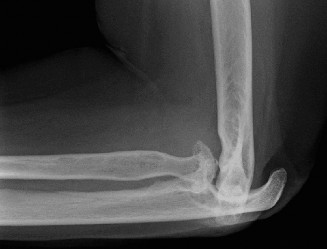

- Plain Radiographs: Anteroposterior (AP) and lateral views are essential. Obtain views of the entire humerus and forearm to assess overall alignment, bone stock, and presence of previous hardware. Look for characteristic RA changes: joint space narrowing, erosions (particularly radial head, capitellum, olecranon, trochlear notch), subchondral cysts, osteopenia, and subluxation/dislocation. Stress views may reveal instability.

The pathophysiology involves sustained synovial inflammation (pannus formation) that erodes articular cartilage, subchondral bone, and ultimately compromises ligamentous integrity. This leads to characteristic radiographic changes including joint space narrowing, subchondral cysts, marginal erosions, and osteopenia. Over time, these changes result in significant bone loss, joint subluxation, and debilitating deformity. The ulnar nerve is particularly vulnerable to compression or traction neuropathy due to synovitis, effusions, or progressive valgus deformity.

In RA, the articular surfaces of all three joints can be severely eroded. The radial head frequently undergoes significant osteolysis and erosion, leading to radial head subluxation or dislocation and contributing to valgus instability. The trochlear notch of the ulna and the olecranon process can also be significantly eroded, resulting in bone loss that complicates implant fixation during arthroplasty.

- Plain Radiographs: Anteroposterior (AP) and lateral views of the elbow are fundamental. Obtain true AP and lateral projections. Evaluate for characteristic RA changes: diffuse joint space narrowing, articular erosions (radial head, capitellum, trochlear notch, olecranon), subchondral cysts, osteopenia, and joint subluxation or dislocation. Assess overall bone stock, particularly at the distal humerus and proximal ulna, which is crucial for implant fixation. Stress radiographs may be considered to evaluate ligamentous instability if not readily apparent clinically.